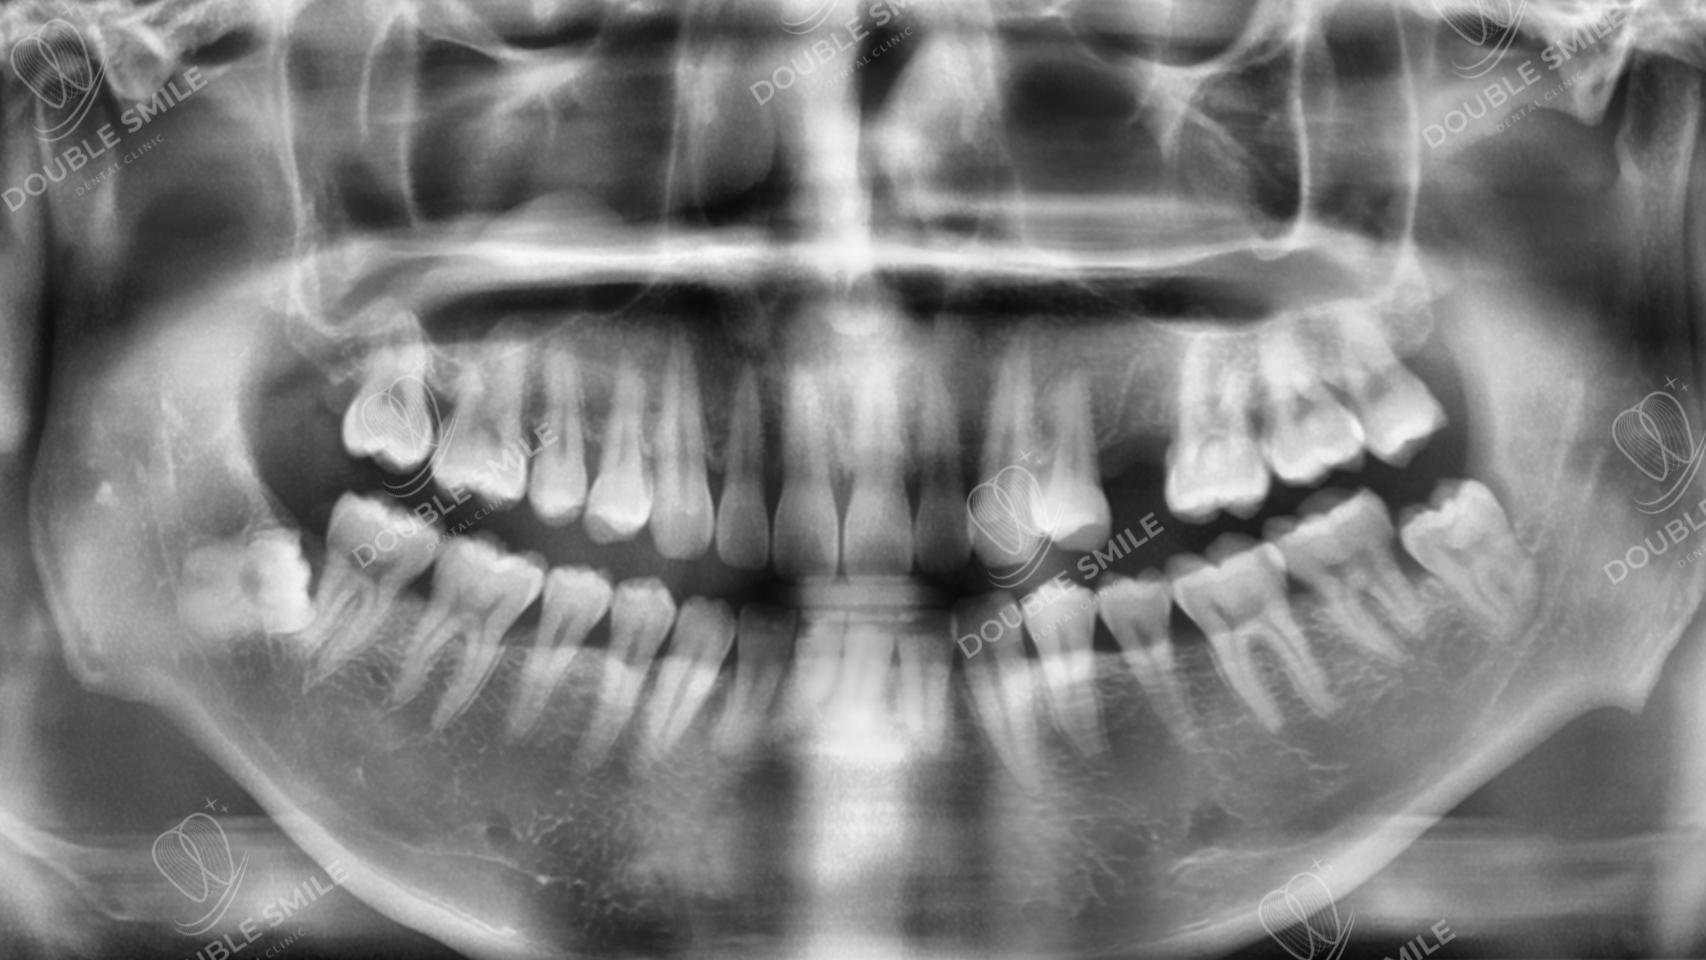

Before